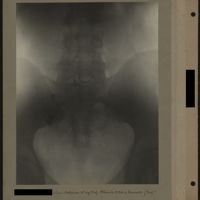

0029 - Page 25 - [Radiographie du bassin]0029 - Page 25 - [Radiographie du bassin]

0040 - Page 36 - [Radiographie du bassin]0040 - Page 36 - [Radiographie du bassin]

0050 - Page 46 - [Radiographie du bassin]0050 - Page 46 - [Radiographie du bassin]

0063 - Page 59 - [Radiographie du bassin]0063 - Page 59 - [Radiographie du bassin]

0071 - Page 67 - [Radiographie du bassin et radiographie du pouce]0071 - Page 67 - [Radiographie du bassin et radiographie du pouce]

0079 - Page 75 - [Radiographie du bassin et radiographie de la main]0079 - Page 75 - [Radiographie du bassin et radiographie de la main]

0086 - Page 82 - [Radiographie du bassin et de la hanche]0086 - Page 82 - [Radiographie du bassin et de la hanche]